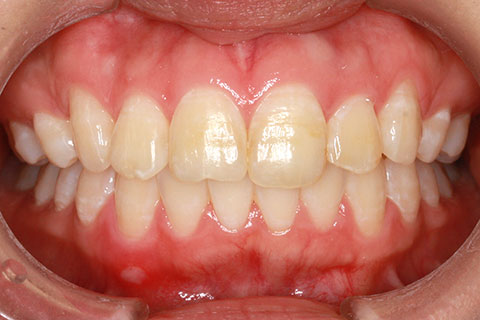

ハーフリンガル矯正3:上の歯のみ舌側矯正で治療(矯正期間24ヶ月)

治療前

治療中(開始直後)

治療中(開始半年後)

治療後

- 年齢・性別

- 25歳女性

- 治療期間

- 2年0ヶ月

- 抜歯

- 上下4番抜歯

- 治療費

- 110万円

- 治療内容

- 施術の副作用(リスク)

- 表側矯正と比較して、力学的な操作性が複雑なため、ボーイングエフェクトを起こしやすい。